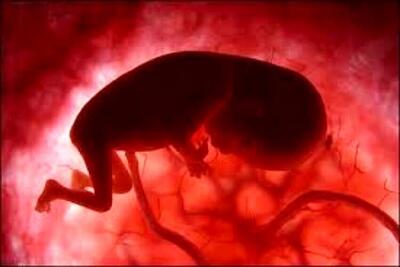

سقط عمدی جنین

عوارض جبران ناپذیر سقط جنین در مراکز غیرقانونی

یک متخصص زنان درباره عوارض سقط جنین عمدی و غیرقانونی در مراکز غیربهداشتی توضیح داد: این کار میتواند باعث عوارض جدی و خطرناک مانند عفونت، خونریزی شدید و آسیب دائمی به رحم و نازایی شود.

خطر داروهای سقط جنین در بازار سیاه/ عوارض سقط از نازایی تا مرگ - تسنیم

عضو تیم تخصصی مرکز درمان ناباروری ابنسینا میگوید سقط جنین عمدی در مراکز غیربهداشتی و غیرقانونی باعث آسیبهای روحی و جسمی به مادران میشود و میتواند منجر به مرگ مادر در پی عفونت و خونریزی شدید شود.

ورود خطرناک داروهای قاچاقی سقط جنین به بازار آزاد / عوارض سقط جنین غیرقانونی؛ از نازایی تا مرگ

رکنا: عضو تیم تخصصی مرکز درمان ناباروری ابنسینا میگوید سقط جنین عمدی در مراکز غیربهداشتی و غیرقانونی باعث آسیبهای روحی و جسمی به مادران میشود و میتواند منجر به مرگ مادر در پی عفونت و خونریزی شدید شود.

90 درصد سقط جنین ها با تصمیم پدر و مادر صورت می گیرد

رئیس مرکز جوانی جمعیت، سلامت خانواده و مدارس وزارت بهداشت گفت: بیش از ۹۰ درصد سقطهای عمدی در چارچوب خانواده صورت میگیرد، یعنی با تصمیم پدر و مادر انجام شده است و این باعث میشود که این نوع سقطها بیشتر شود.

اثرات سقط غیرعمدی پس از ۶ ماه از بین میرود، اما اثرات سقط عمدی تا سالها می ماند + فیلم

عوارض جدی سقط جنین برای ۸۰ درصد از مادران

کارشناس مامایی دانشگاه علوم پزشکی قزوین گفت: سقط جنین، روشی برای پایان بارداری است که گاهی عمدی و گاه ناخواسته انجام میشود ۸۰ درصد مادرانی که سقط جنین میکنند، دچار عوارض جسمی یا روحی میشوند.

رئیس مرکز جوانی جمعیت: مسائل اقتصادی علت اول و اصلی سقط عمدی نیست

رئیس مرکز جوانی جمعیت وزارت بهداشت گفت: پژوهشهای مختلف نشان میدهد که مسائل اقتصادی، علت اول و اصلی سقط جنین عمدی نیست و ۶۰ درصد علل این کار در کشورمان ناشی از انگارههای ذهنی است.

جنینها در آرزوی مشایه!

شاید اگر فهم درست از جنین و حیات جنین وجود داشته باشد آمار قتل عمدی جنینها کمتر شود.